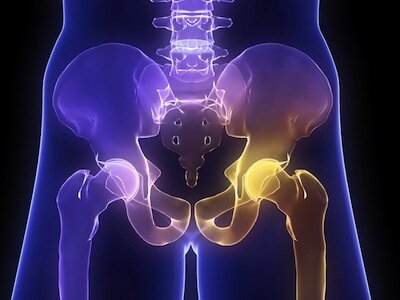

• DENSITOMETRÍA ÓSEA: Introducción

DENSITOMETRÍA ÓSEA: Introducción

Se introdujo la radiografía cuantitativa y la radiogrametría.

Se introdujo la densitometría o absorciometría fotónica simple.

• DENSITOMETRÍA ÓSEA: Absorciometría

DENSITOMETRÍA ÓSEA: Absorciometría

Cameron y Sorenson describieron la absorciometría de fotones

• DENSITOMETRÍA ÓSEA: Densitometría Fotónica Dual

Se propusieron las aplicaciones clínicas de la densitometría fotónica dual.

DENSITOMETRÍA ÓSEA: Densitometría Fotónica Dual

• DENSITOMETRÍA ÓSEA: SP2

DENSITOMETRÍA ÓSEA: SP2

Se empezó a comercializar el equipo denominado SP2 que con una fuente permitía con razonable exactitud medir el contenido mineral óseo. Esta medición se realiza mediante la absorción de doble fotón.

• DENSITOMETRÍA ÓSEA: Comercio de la densitometría fotónica dual

DENSITOMETRÍA ÓSEA: Comercio de la densitometría fotónica dual

Se comercializó la densitometría fotónica dual y después la densitometría dual por rayos X, conocida habitualmente como DEXA dondé se podía medir la densidad óseo de hueso periférico y columna vertebral.